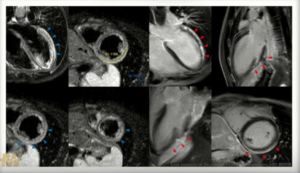

One of the many fatalities from vax-induced myocarditis (heart inflammation) came after 26-year-old Joseph Keating’s third jab on Nov. 8, 2021. The young South Dakota man died just four days after his Pfizer booster.

An autopsy confirmed the vax was responsible: “myocarditis in the left ventricle due to the recent Pfizer COVID-19 booster vaccine.” From what we know about spike protein damage to the heart (occurring disproportionately in young males), chances are that his cardiac injury began developing over the first two shots and the booster was the final straw.

“When the pathologist looked at the 22 segments of Joseph’s heart, it showed the vaccine inflamed and attacked his entire heart. There was so much damage… It was full multi-focal myocarditis, and it wasn’t just affecting one part of his heart, it was attacking his whole septum and ventricles.”

The CDC—which, like Berry, has swept this kind of devastating heart damage under the rug—has not investigated his death.

Our last reporting on heart damage from the shots focused on the increasing incidence in young people. Those mounting injuries and deaths are underscored by the local tragedy of a 27-year-old Port Townsend woman who recently suffered two life-threatening heart attacks just days after injection. The formerly healthy, active woman we called Laura is now living at great risk with acute myopericarditis. (See Young Heart Damaged by Pfizer Vax.)